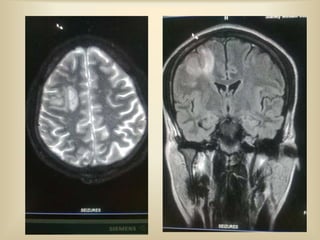

MRI BRAIN REPORT

 MRI brain shows T1 hyperintense / non

suppressible T2 hyperintensity in the right

high parietal lobe. The lesion shows

peripheral blooming in T2 gradient sequence

suggestive of hemorrhage.

 Absence of flow voids in mid sagittal and

transverse sinus in FLAIR images suggestive

of sinus thrombosis

 T1 hyperintensity noted in superior sagittal

sinus and right transverse sinus suggestive of

thrombosis.

 MR venography confirms the evidence of

thrombosis in superior sagittal sinus and right

transverse sinus.

T2 hyper

intensity

Gradient

blooming

T1

hyperintensity

FLAIR

FLOW

VOID